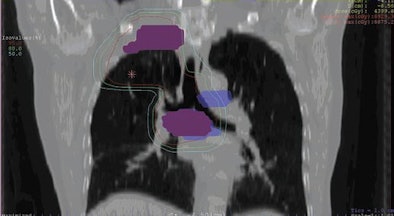

| Images are of a 62-year-old man with NSCLC. Initial pre-FDG-PET and clinical target volume (CTV) are represented in blue and red, respectively, on frontal (above) and transverse (below) images. FDG-PET images resulted in a decrease of mediastinal CTV and treated volume. Isodose lines represent dose distribution (95%, 80%, 50%, and 30% of prescribed dose). Images courtesy of the American Journal of Roentgenology. |